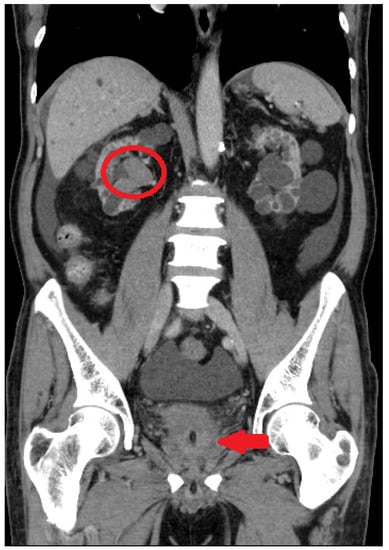

2.1. Initial Assessment

2.2. Robot-Assisted CUTE